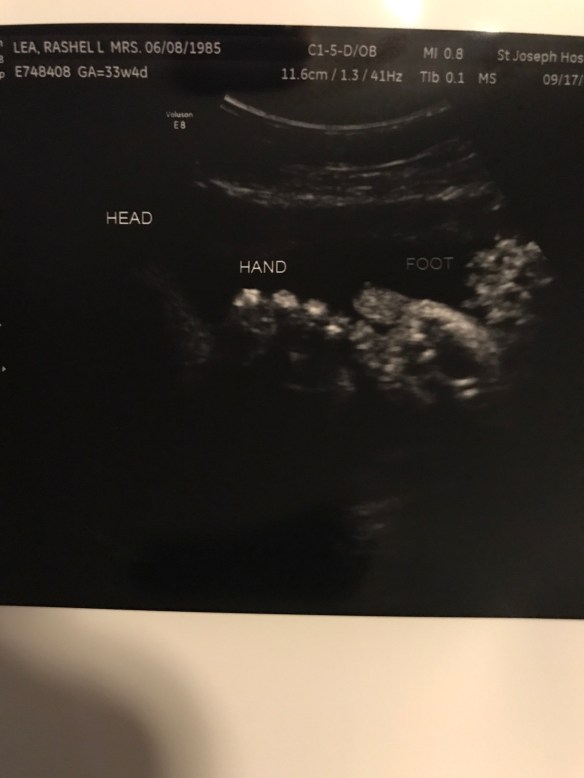

Well the last 4 weeks has been quite a whirlwind. During some of our ultrasounds baby B was measuring just a little behind in his legs. I didn’t think much of it but my dr decided to send us to a specialist just to make sure. She basically said worst case scenario would be dwarfism and best case would be he’s just short. Obviously that was not what anyone wanted to hear. We all want our babies to be as perfect as they can be. We had to schedule out the appointment for about a week or two after. Lucky they got us in pretty quickly! We were able to get great news this week that he looks just fine! Yes his legs are a little short but he seems just fine! What a relief this was for J and K! So we had our regular OB appointment today and he still looks good except for he won’t move to the head down position!!!! He likes to be transverse. He’s a stinker. So we will now be trying acupuncture! I’m also trying the warm on the bottom of my belly and the cold by his head to encourage him to move south! We still have time for him to get it together. Obviously I want to avoid a c section. I feel terrible and selfish sometimes saying that… obviously if it’s an emergency or nothing can be done then I just want him here safe and sound with his parents. I just know how hard it was physically and emotionally for me to heal after my one c section. It’s way more painful and takes a lot longer to get back to normal. So send me all the prayers and good vibes you guys have for a wonderful safe vaginal delivery! Exciting news J was able to feel baby B move around a bit! We tried to guess what part of his body it could possibly be! In all of his pictures he likes to keep his hands and feet right by his face! We’re actually impressed how he does it! He’s a little acrobat! So I have acupuncture next week then the next week A regular ob appointment. Then I go every week so at my 37 week we will have another growth scan at the specialist and then another ob appointment to check me! My dr will be out of the office for that appointment but will be back for the next one I believe! Oh we also did hospital tours while they were in town! That’s fun for them! I remember feeling excited to pick where I was having my baby. I wanted them to have the same experience that most get. Well I believe that’s all I have for right now. I’ll add some pictures for fun!